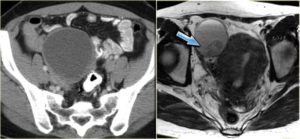

Компьютерная томография

Обычно дермоидные кисты представляют собой хорошо отграниченные, дольчатые образования сниженной (жировой) плотности. В стенке могут встречаться кальцинаты.

Контрастное усиление не характерно и если присутствует, то должно быть в виде кольца по периферии.

Редко, дермоидные кисты имеют включения высокой плотности за счет сапонификации (омыления солей кальция), микрокальцинатов и продуктов распада гемоглобина.

ЛКТ

Лучевая диагностика является одной из распространенных форм рентгенографии. Результаты лучевой компьютерной томографии являются максимально информативными.

Процедура проводится путем воздействия рентгеновских лучей на исследуемую область, позволяет определить характер развития новообразования.

Данная процедура является важным методом исследования тератомы, поскольку существует минимальный риск перерождения дермоида в злокачественную опухоль.